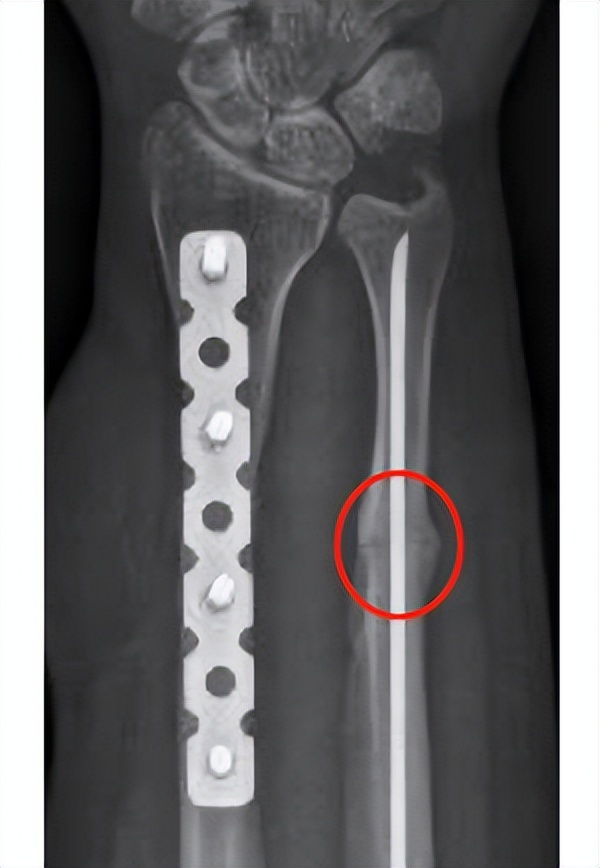

大家一定很关心,这么微创的治疗方式,能不能治愈这个骨不连。这是病人手术治疗后3个月回来复查的X线片,大家可以看到骨不连的区域已经完全实现了骨性的愈合,间隙已经消失了。

(生长因子注射术后3个月)